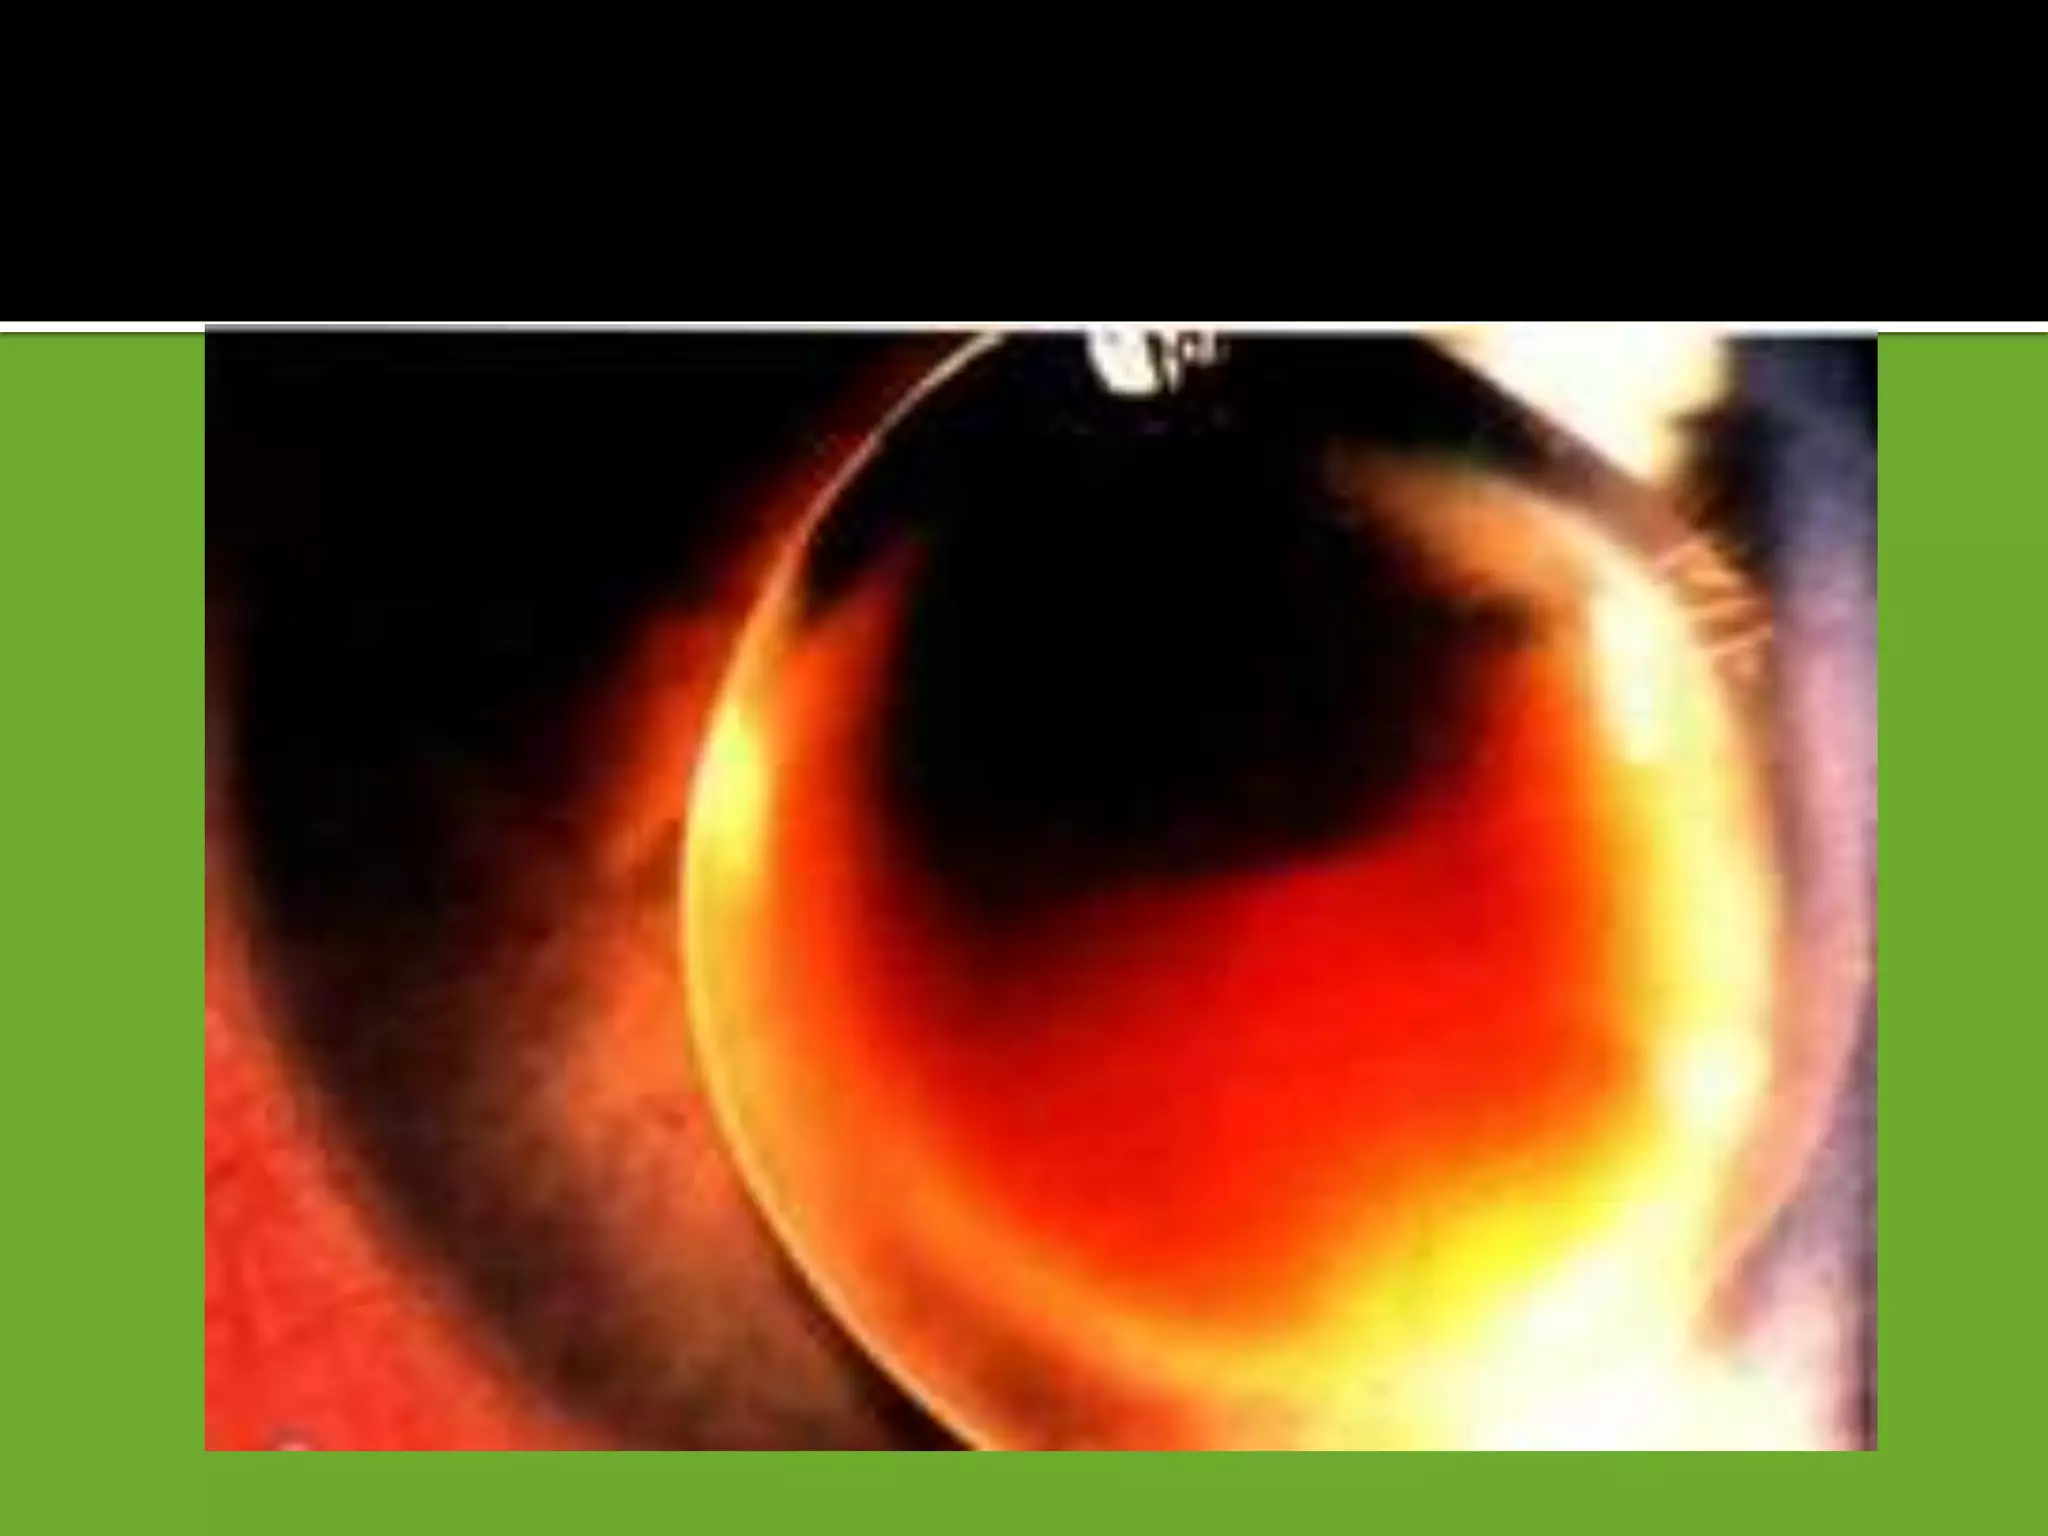

1 Penetrating trauma

2 Blunt trauma may cause a characteristic flower-shaped

opacity

 A ring-shaped anterior subcapsular opacity may underlie a Vossius

ring [. Imprinting of iris pigment on anterior lens capsule]

 Commonly opacification occurs in the posterior subcapsular

cortex along the posterior sutures, resulting in flower -shaped opacity